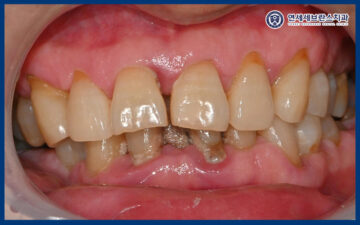

위 환자분께서는

예전부터 왼쪽 아래가 충치 때문에 아프더니

3일 전부터 오른쪽 아래 잇몸이 많이 붓고

통증이 극심해서 참기 어려워

급하게 본원에 내원해 주셨습니다.

예전에 갔던 타 치과에서는

치아 뿌리 끝 염증이 너무 심해서

큰 문제가 생길 수도 있고,

어금니는 다 뽑고 임플란트를 해야 한다고

들으셨다 하셨습니다.

어금니가 대부분 소실된 상태로,

식사를 위한 저작 기능 회복을 위해서는

임플란트 치료가 필요한 상황이었습니다.